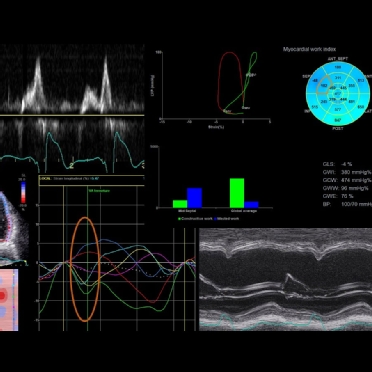

Multimodality Imaging CRT Toolbox

Learn about cardiac resynchronization therapy (CRT), cardiac mechanic and mechanical dyssynchrony with this selection of courses and resources brought

to you by the best European experts.